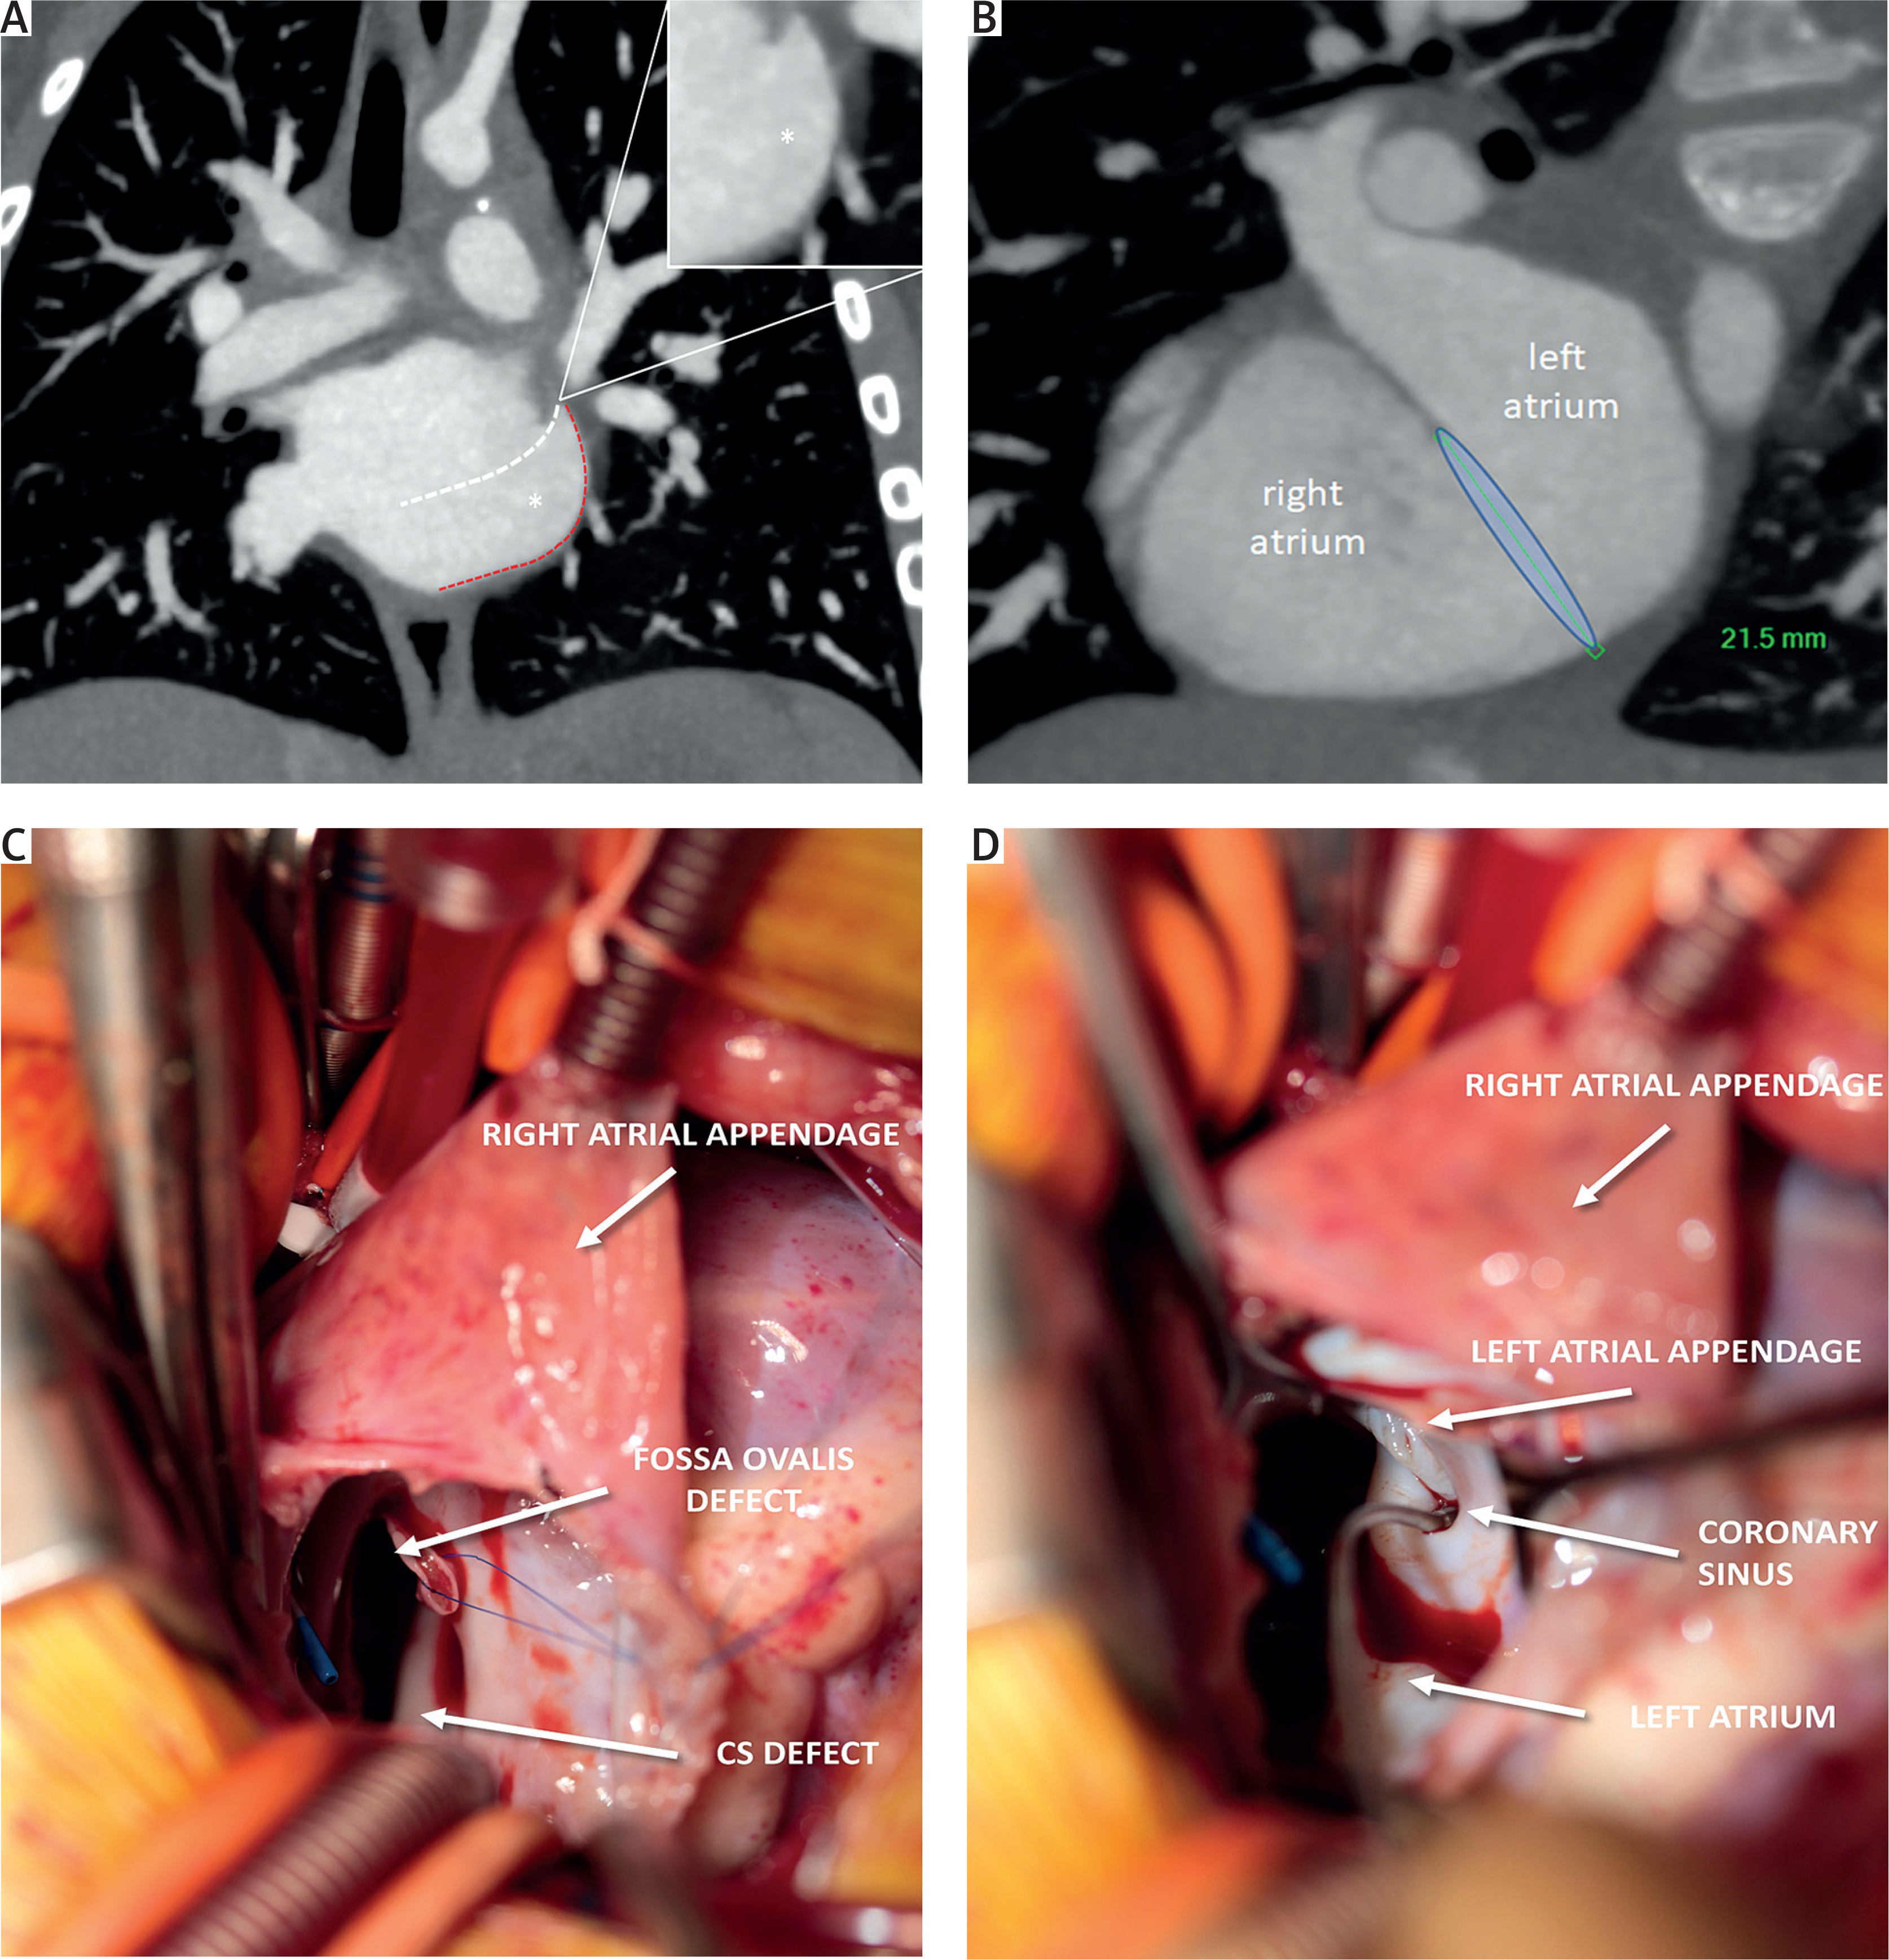

Figure 1

A – Completely unroofed coronary sinus (CS) (white dashed line) without persistent left-superior vena cava – coronal view. Red dashed line represents the bottom of the coronary sinus. Asterisk represents the beak of the coronary sinus. B – The diameter of the interatrial communication was approximately 2 cm. C, D – Perioperative findings. The surgical probe tip points to the ostium of the CS in the left atrium

We illustrate the case of a 1.5-year-old girl presenting with failure to thrive and a heart murmur. The diagnosis of sinus venosus atrial septal defect with unroofed coronary sinus was suggested by echocardiography. Due to unclear delineation of a complete CS, the patient underwent cardiac computed tomography angiography (CCTA). CCTA confirmed a completely unroofed CS (Figure 1 A, white dashed line) without persistent left-superior vena cava (L-SVC). The only developed part of the CS, visible on CT, was the bottom of the CS (Figure 1 A, red dashed line) and a “beak” (Figure 1 A, *) located between the left atrial appendage (LAA) and the left lower pulmonary vein. The diameter of the interatrial communication was approximately 2 cm (Figure 1 B). Both the right atrium and right ventricle were qualitatively enlarged.

The patient was discussed within a multidisciplinary heart team, and was subsequently referred for surgery. The completely unroofed CS was confirmed perioperatively. Moreover, a confluent atrial septal defect (fossa ovalis plus CS type) was found (Figure 1 C). After administering an antegrade cardioplegia solution, the ostium of the CS in the left atrium (LA) was identified. The surgical probe tip points to the ostium of the CS in the LA (“beak” on CT, Figure 1 D). The defect was surgically repaired using autologous pericardial patch closure, and the CS was left to drain into the LA. The observed mild desaturation, a typical outcome of this procedure, was deemed acceptable. The post-operative transesophageal echocardiography demonstrated no residual shunt and normal systolic function. The postoperative course was uneventful, and the patient was discharged on the fourth day after surgery. At follow-up, the patient exhibited a favorable clinical course, characterized by preserved ventricular function and the absence of residual shunting.